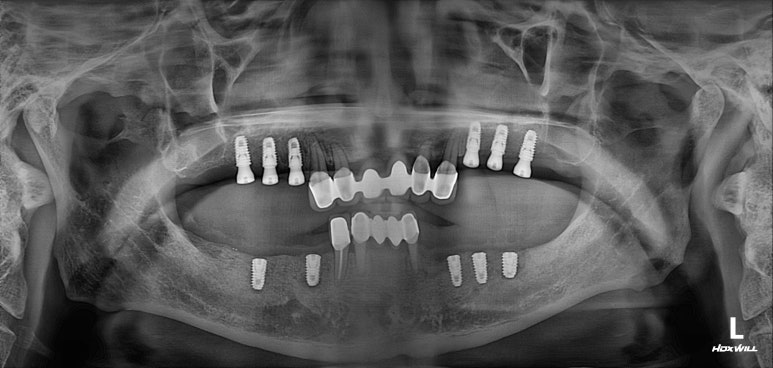

양쪽 위 어금니 부위에 깔끔하게 3개씩 임플란트를 심어드렸습니다.

이 3개의 임플란트는 시간이 흘러 첫번째, 두번째 작은 어금니 그리고 첫번째 큰 어금니가 됩니다.

치과용 파노라마 사진 상에서 잘 확인하기 어려우실 수 있지만,

화살표로 표시해둔 곳까지 측방접근법 상악동 뼈이식술이 성공적으로 잘 된 것을 확인할 수 있습니다.

원가이드를 활용하여 2주 후 아래턱 임플란트 수술!

약 2주 후 아래턱 임플란트 수술을 시행하였습니다.

개수가 조금 더 적어보이는 것은, 아래턱 뼈가 위턱뼈보다 더 딱딱하기 때문입니다.

비교적 적은 임플란트로도 성인 남성의 씹는 힘을 견딜 수 있거든요!!!

한편으로 상악동 뼈이식술까지 필요했던 케이스이니... 더더욱이 위턱뼈엔 임플란트가 많이 필요했던 상황이었죠.

아래턱까지 임플란트 수술하고 약 1달이 지난 시점입니다.

뼈이식을 많이했던 오른쪽 위 어금니 부위에 임플란트가 살짝 비춰보이긴 하나, 대체로 잘 치유되고 있는 상황입니다.

아마, 임시틀니를 사용하시는 것이 보다 느린 치유를 만들어내는 원인 중 하나였던 것 같습니다.